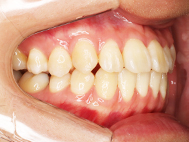

Before

左上の前歯内側に入っている下の前歯ガチャ歯

左上前歯が下の歯の内側に入っているのが気になるとの事で来院されました。目立たない矯正治療を希望しているとのこでした。 上顎の装置は、歯の裏側(リンガル装置)で下顎は表側で矯正治療を行いました。口を閉じた時、上の前歯が内側に入っている為に下の歯を前に押し出している状態でした。その為、上の歯を前に出すだけではその歯が下とのかみ合わせの関係で、前に飛び出すような治療となってしまいます。 今回の症例ではシュミレーションを見て頂き、下の歯も治療し、内側へ下げることによって上の歯も飛びだすことなく、キレイにおさまることを説明し、上下一緒に矯正することをお勧めさせて頂きました。